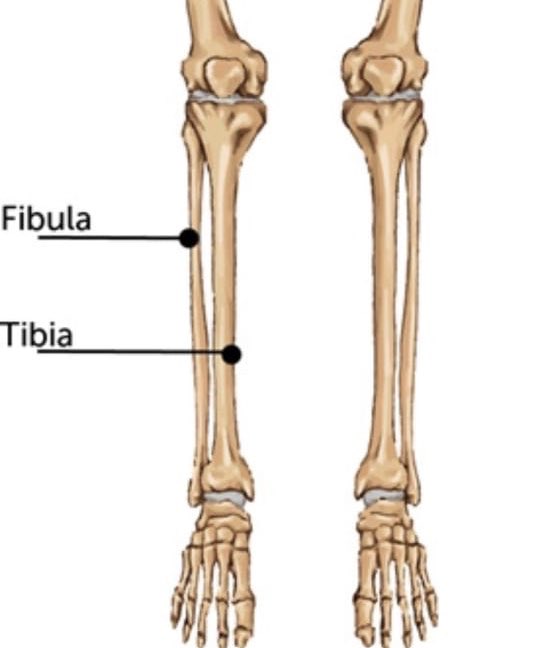

Анатомия фибулы: Подробные фотографии и схемы